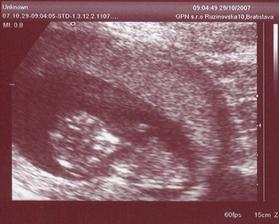

Bocian dorazil o viac ako mesiac skor (ukecal som ho, uz ma to tam nebavilo...) a tak som sa miesto 15.5. narodil 11.4. Mal som vsetko co som mal mat /2790g a 48cm pri porode/ a tak po ohriati sa par dni v inkubatore a zltacke sme prchali z porodnice s pripisanou vahou po 12-tich dnoch - uz sme tam nemohli dalej vydrzat! :o) Nastastie jedna zlata sestricka nam pomohla sa odtial dostat za co jej velmi pekne dakujeme! Dalsie fotky su v mojom druhom albume...